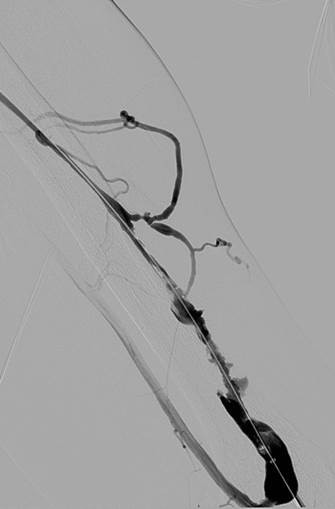

Fistulograma que demuestra la oclusión trombótica de una fístula AV braquiocefálica izquierda (nota: reflujo arterial de contraste).

Tras la primera pasada con el catéter DVX de AngioJet (no se usaron trombolíticos).

Tras la segunda pasada con el catéter DVX y la angioplastia con balón de la estenosis subyacente. Sin impedancia para el flujo de avance en la FAV.

Una vez que se establezca el flujo de avance y se trate la estenosis, los trombos residuales deberían resolverse.